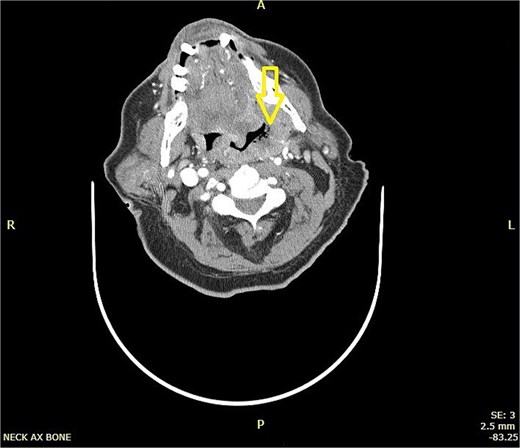

CT scan neck with contrast (Figs 1 and 2):

CT scan of neck showing a hyper-dense lesion in the tail of the right parotid gland measuring 1.3 × 0.9 cm (AP, TV dimensions) with no deep extension. The left tonsil is enlarged with faint, il-defined rim enhancement, and central air foci, indicating early abscess formation.

CT left parotid hyper-dense lesion, which may indicate lymph node metastasis or primary tumor. For pathological correlation (which showed Warthin tumor) and early left tonsillar abscess for clinical correlation.